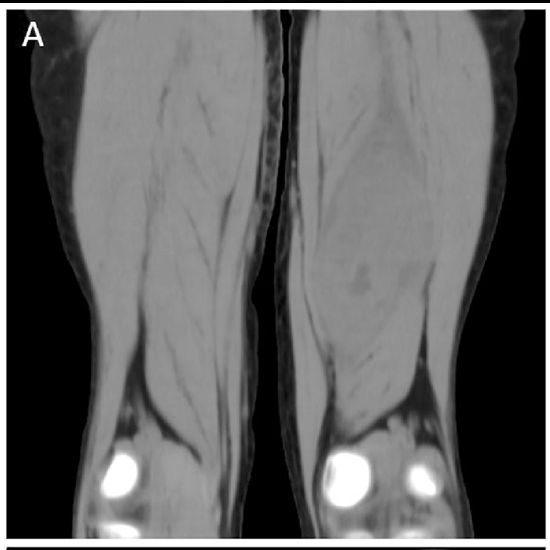

CT B/L Thigh & Leg acronyms for computed tomography for bilateral thigh and leg. It is an imaging scan used to obtain cross-sectional images of both thighs and legs. It is used to diagnose an abscess, infection, broken bone, masses, fractures, and tumours that cause a problem in the thighs, foot, ankle, and knee joints.

The doctor recommended CT B/L Thigh & Leg to diagnose a bone fracture, bone deformities, broken bones, cause of infection and pain, tumours, etc. that cause problems in the bilateral thigh, foot, ankle as well as knee joint.